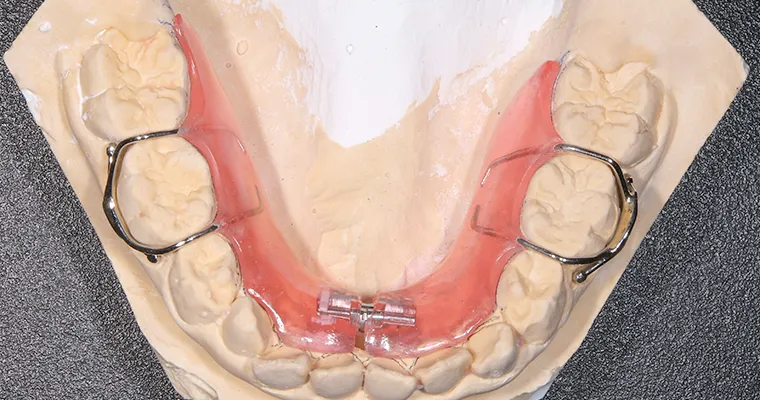

使用矯正装置 上

使用矯正装置 下

| 主訴 | 幼少期から反対咬合 |

|---|---|

| 治療期間 | 10ヶ月 |

| 治療費 | 440,000円(税込) ※調整、器具、治療後にお渡しするEFLine(矯正後の後戻りを防ぐ器具)も全て込みでの金額となっております。 |

| 治療内容 | 6歳で上下拡大 上顎牽引装置 EF Lineで筋機能療法 |